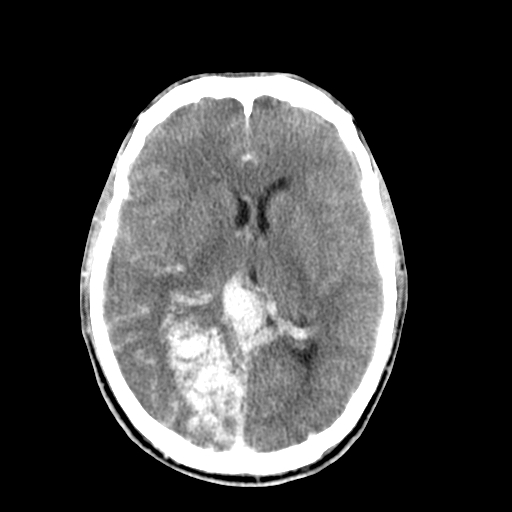

标题: CT17002:M48Y,血管畸形,血管瘤,请鉴赏! [打印本页]

男48y,头痛多年,加重一天!

典型的血管畸形---avm  -----右侧枕顶叶及侧脑室三角区等高混杂密度影夹杂少许低密影显示,无明显水肿,增强可见明显的供血动脉与引流静脉显示